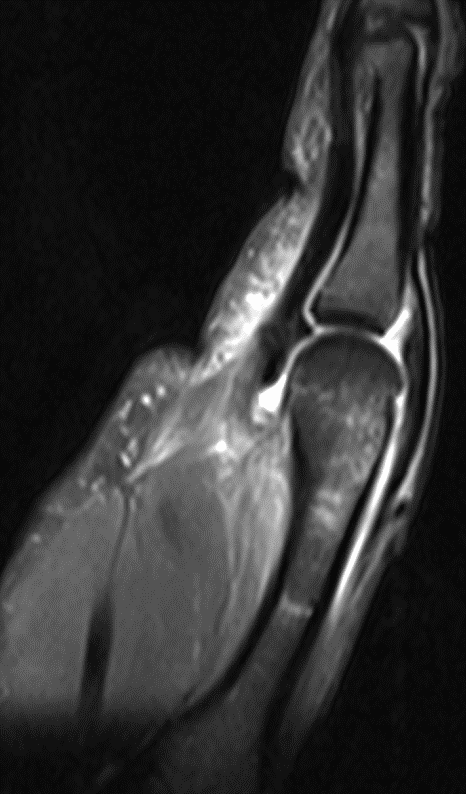

МРТ кисти и лучезапястного сустава — самый информативный метод диагностики, дающий возможность оценки состояния костно-суставных и мягких тканей.

Показания к МРТ кисти и лучезапястного сустава: спортивные, производственные и бытовые травмы кисти и лучезапястного сустава, в том числе повреждения связочного аппарата кисти, хрящей, разрывы капсулы лучезапястного сустава и связок запястья, инородные тела, ущемление сухожилий, а также ущемление нервов (карпальный туннельный синдром), заболевания связочно-мышечного аппарата кисти и лучезапястного сустава различной природы (теносиновиты, гигромы, контрактура Дюпюитрена, флегмона и др.), заболевания суставов различной природы (артриты, артрозы, поражение суставов при коллагенозах, сахарном диабете, подагре, остеомиелите и т.д.) – все эти виды патологии кисти и лучезапястного сустава с высокой степенью достоверности можно установить с помощью МРТ. Показаниями к проведению МРТ являются противоречивость клинических данных и неясность или отсутствие характерных рентгенологических признаков повреждений области лучезапястного сустава, болевой синдром и нарушение функции кистевого сустава неясного генеза, в том числе при отсутствии травмы в анамнезе. Магнитно-резонансная томография является эффективным методом диагностики не только повреждений кистевого сустава и их последствий, но и мониторинга результатов проводимого лечения, так как обеспечивает возможность комплексной визуализации костных и мягкотканных структур этой области. МРТ кистевого сустава целесообразно проводить всем пациентам на начальном этапе лучевого обследования после рентгенологического исследования при травме кистевого сустава и неясной клинико-лучевой картине, а также при тяжелой травме со значительными повреждениями костных и мягкотканных структур, либо при болевом синдроме и нарушении функции в суставе неясного генеза при отсутствии травмы в анамнезе.